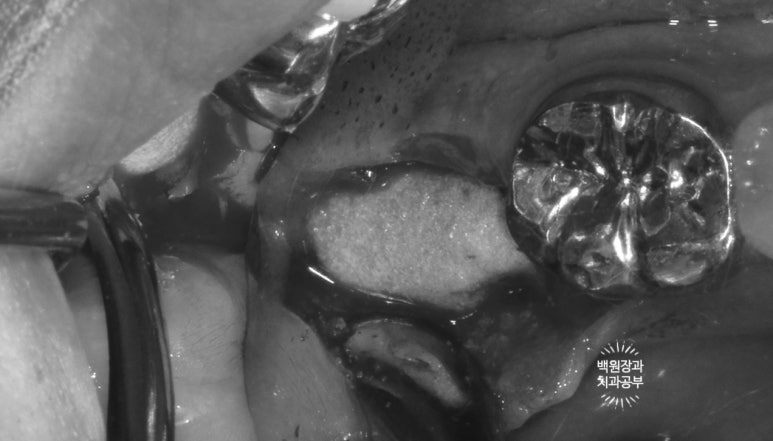

환자분의 사정으로 8주를 기다리고 잇몸뼈 내부를 살펴보았지만, 아직도 치유가 더딘 것이 보이죠?

일단 임플란트를 정위치에 위치시키고, 오스템 임플란트를 사용하여 수술하였습니다.

부족한 부위는 합성뼈로 채워넣었습니다.

저희 연세더좋은플란트치과는 덴티움의 osteon III를 사용하고 있답니다!

오랜 역사와 전통을 가진 국내산 뼈이식재라고 표현하면 알맞을 듯 해요 :) 명품이라고 생각합니다.

그리고 같은 덴티움 사의 dentium collagen membrane (차폐막)을 이용하여 골이식재 상방을 덮어주었습니다.

제대로 된 뼈이식을 하려면 골이식재를 차폐막으로 무조건 덮어주어야 합니다! 말뿐인 골이식재가 아니라 확실한 결과를 얻기 위해선 학문적으로 차폐막의 사용은 필수입니다.